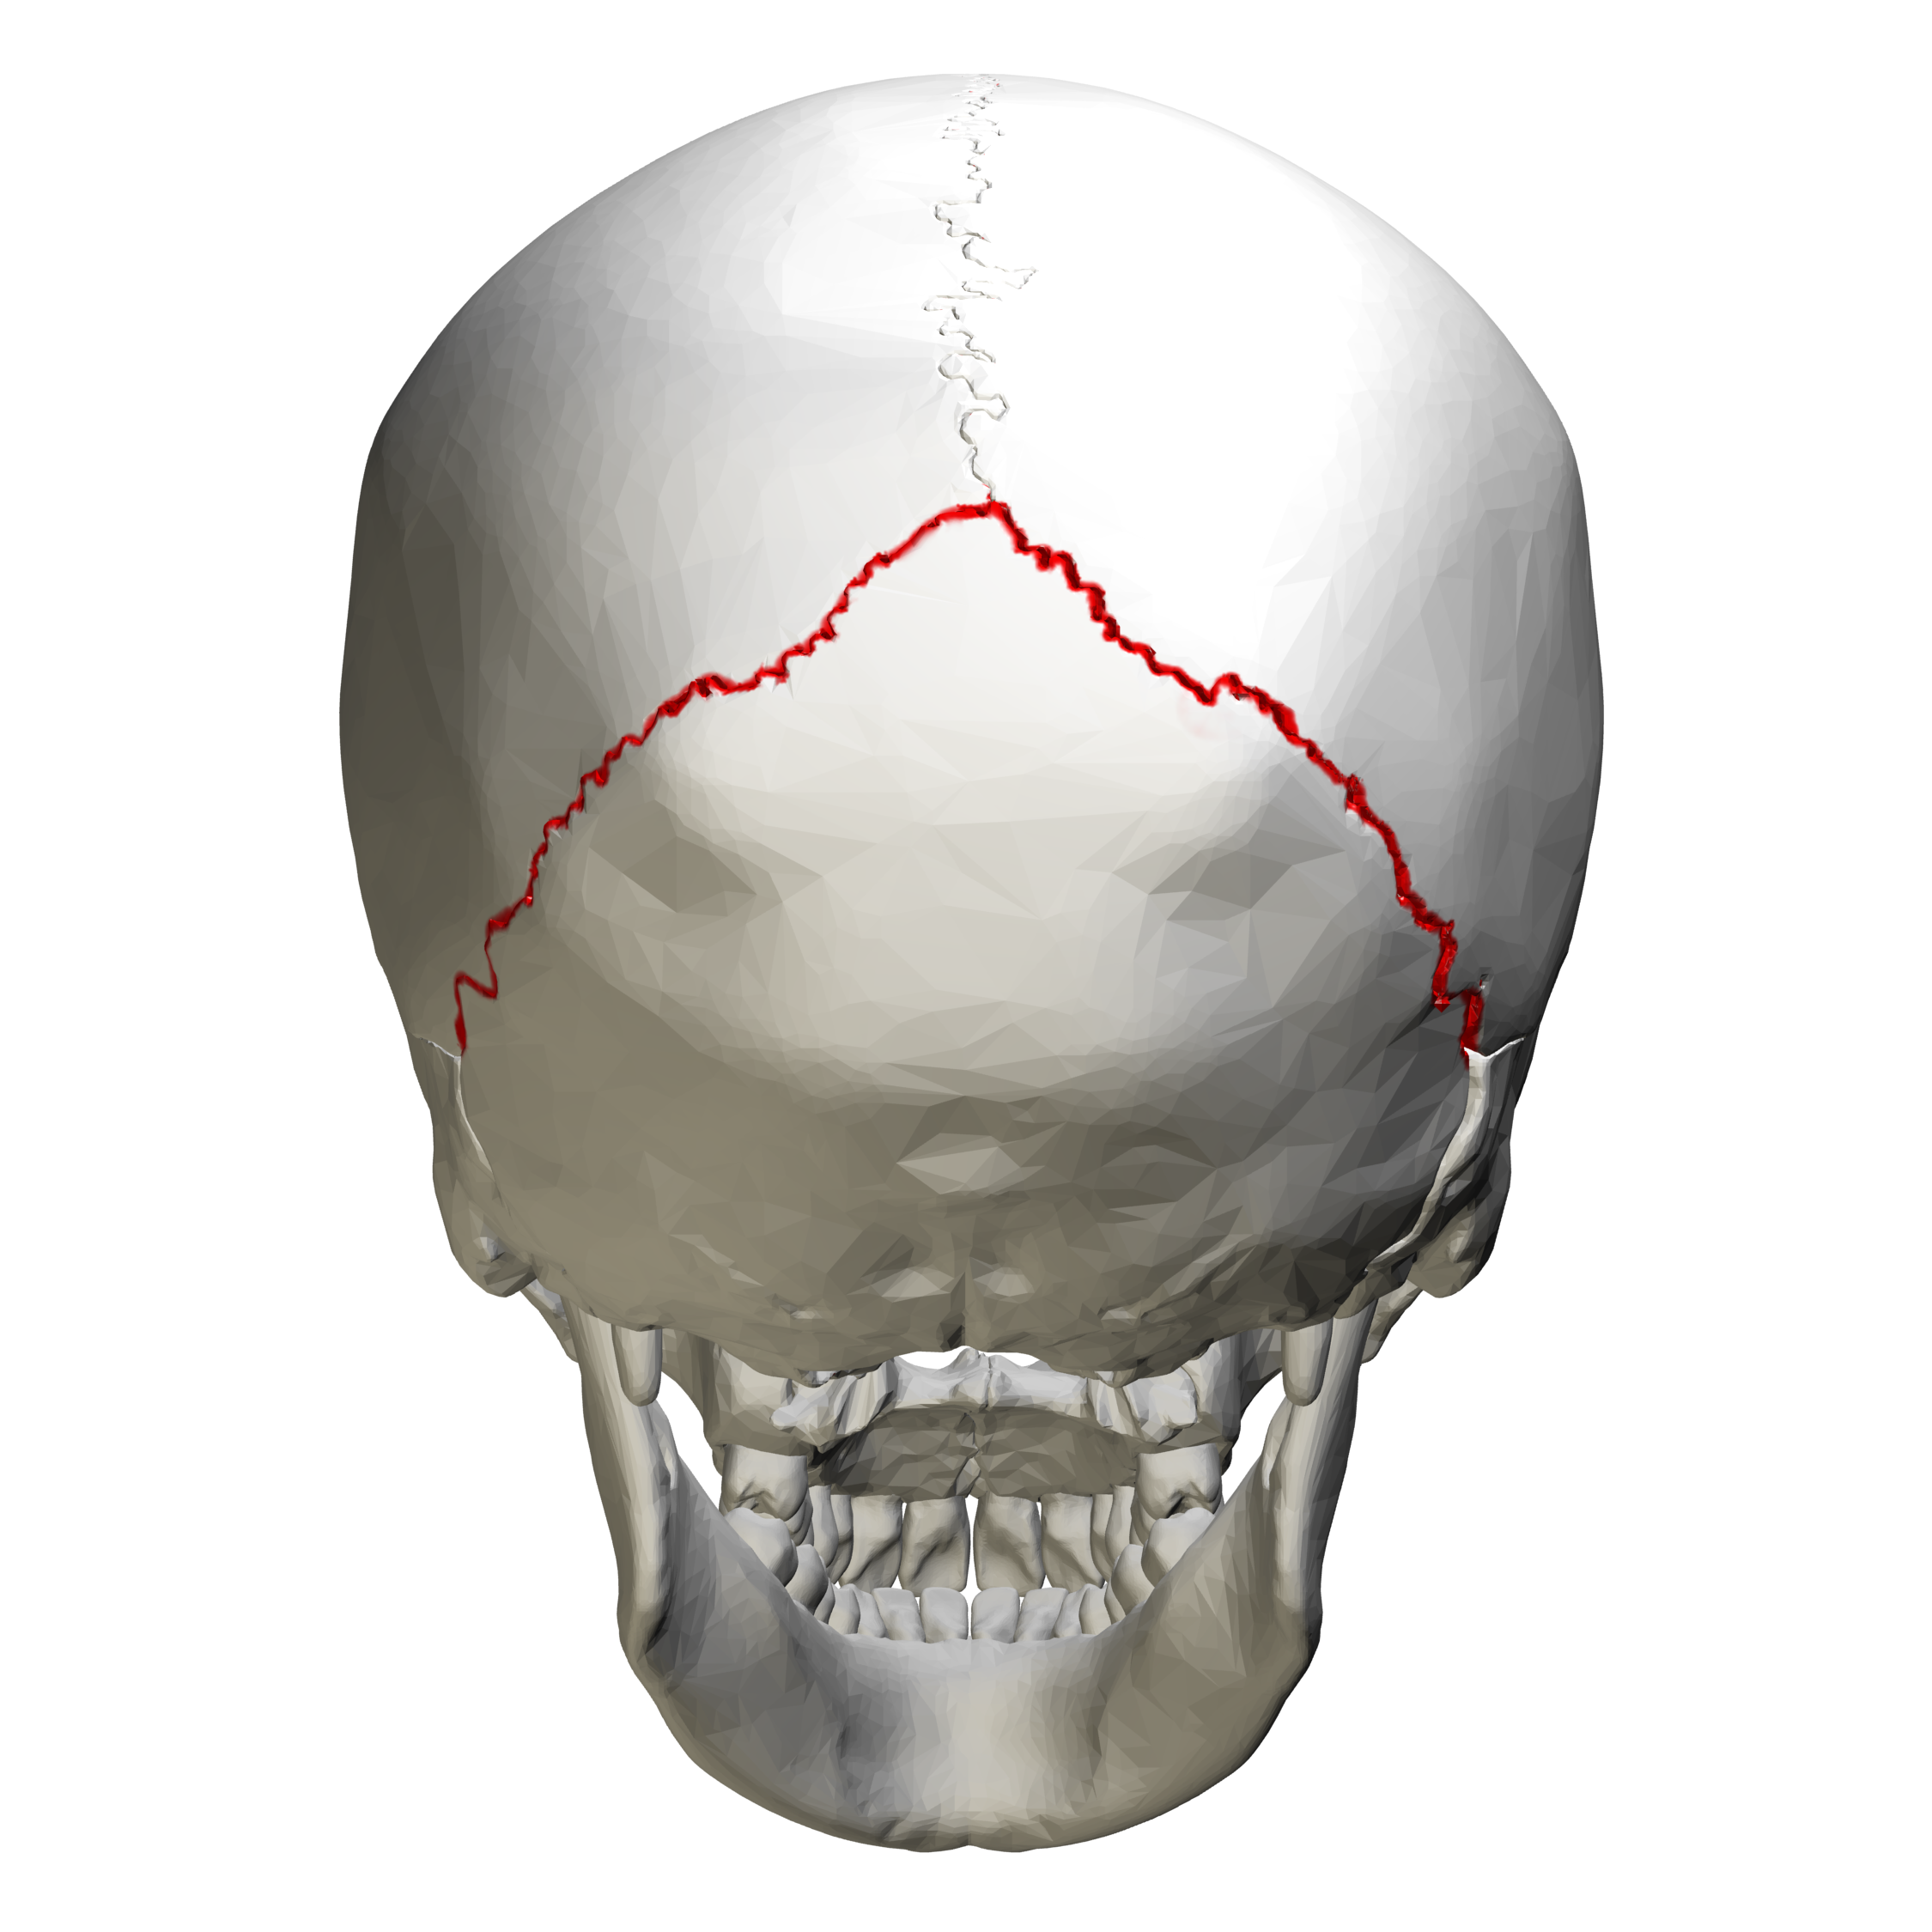

lambdoid suture